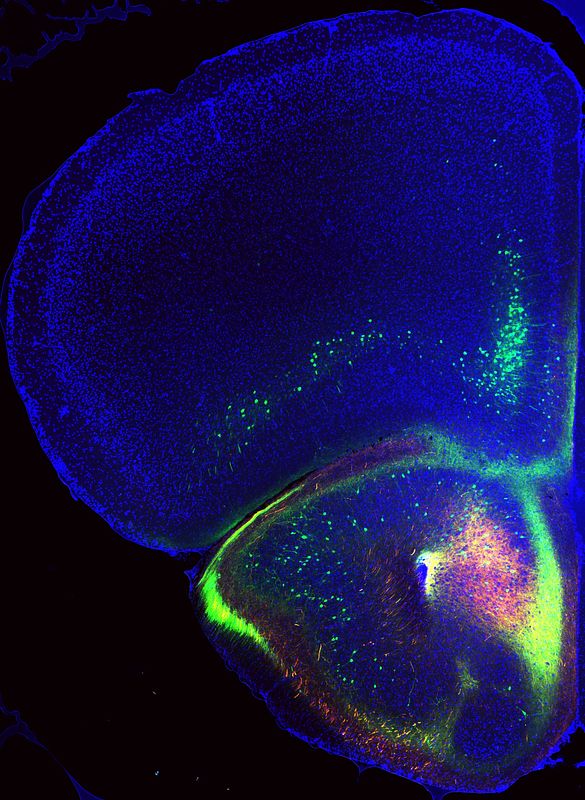

We focus on a direct pathway from the medial OFC to the medial amygdala, a key node in aggression circuits. Using circuit-specific tracing, in vivo calcium imaging, and chemogenetic manipulation, we find that this pathway is excitatory, strongly activated during traumatic stress, and required for the later emergence of aggressive behavior.

Mapping of excitatory medial orbitofrontal inputs to the medial amygdala